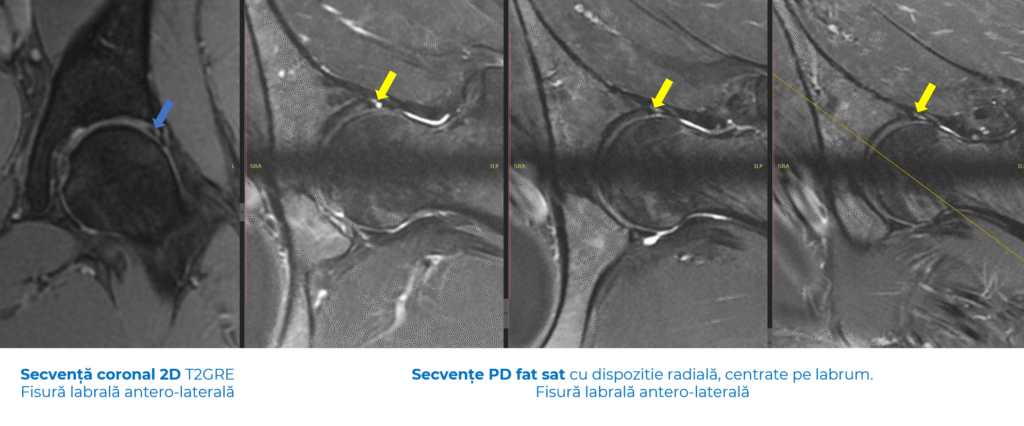

- Ruptura de labrum

Labrumul este un inel de cartilaj care înconjoară articulația șoldului și are rol de stabilizare și amortizare. O ruptură poate provoca durere profundă, „pocnituri” sau senzația de blocaj la anumite mișcări.

De multe ori trece neobservată la RMN standard, însă poate fi evidențiată prin investigații dedicate, interpretate de radiologi specializați pe musculo-scheletal.

- RMN-ul convențional – rămâne esențial pentru analiza țesuturilor moi (labrum, cartilaj, mușchi, capsule articulare).

- Artro-RMN-ul (rezonanță magnetică cu substanță de contrast) – aduce un plus de acuratețe în depistarea rupturilor de labrum și a leziunilor de cartilaj.